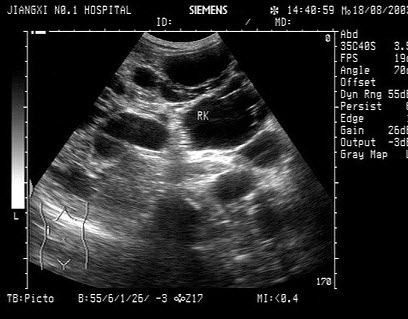

203、单项选择题

男,有高血压病史,腰部触及包块,超声检查如图所示,最可能的诊断是()